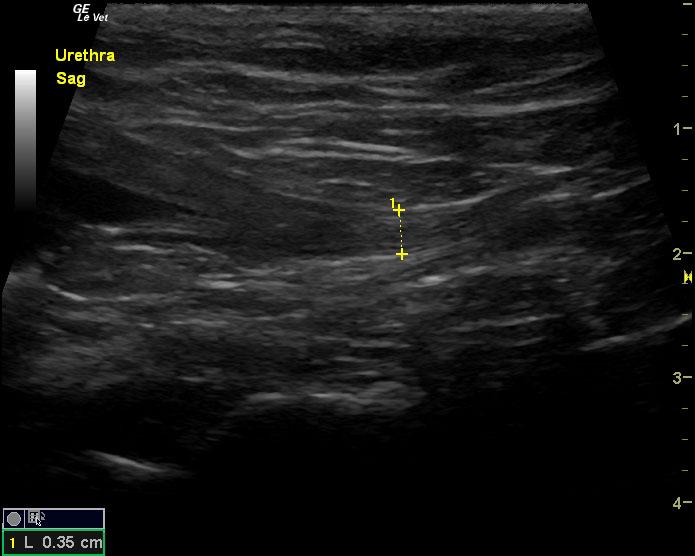

A 6-year-old SF DSH cat was presented for evaluation of chronic cystitis that was non-responsive to antibiotic and Adequan therapy. Both urinalysis and urine culture were within normal limits.

A 6-year-old SF DSH cat was presented for evaluation of chronic cystitis that was non-responsive to antibiotic and Adequan therapy. Both urinalysis and urine culture were within normal limits.